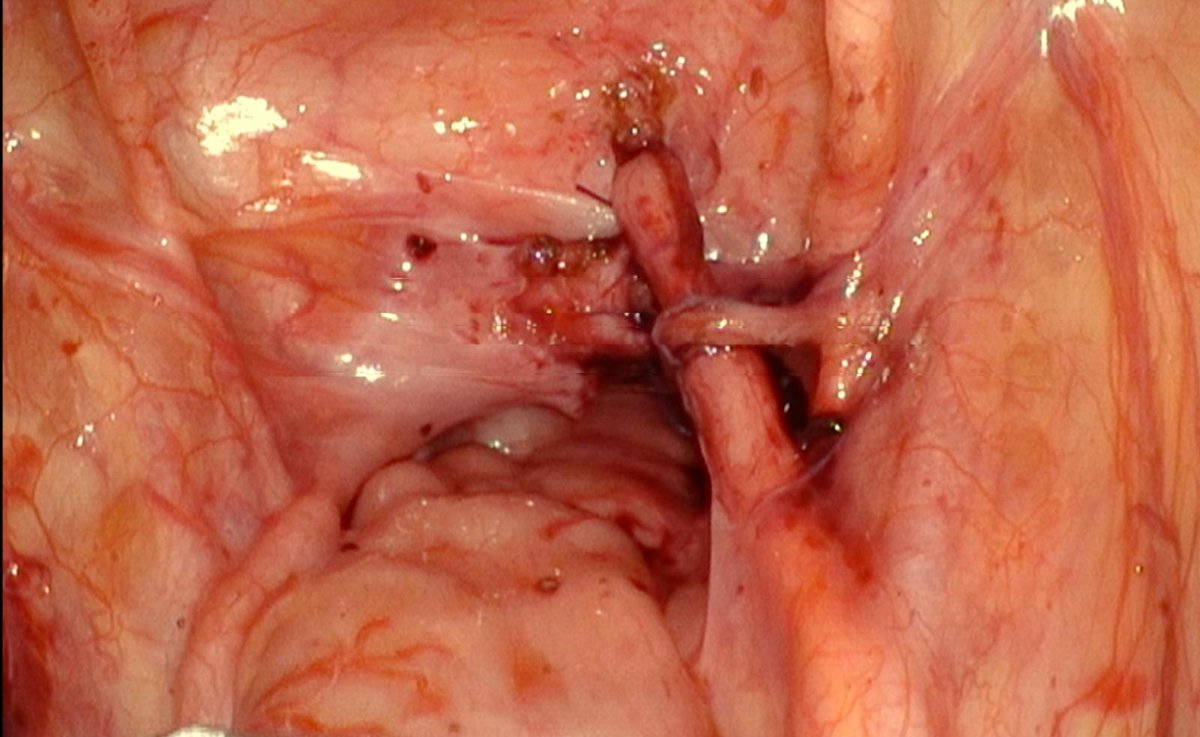

youtu.be/jRU0Fjr4Jo8 A 32-year-old woman presented with a low-lying vesicovaginal fistula near the ureteric orifice following a cesarean section. ROBOTIC VVF repair was performed without the need for ureteric reimplantation. Two sutures were placed close to the ureteric

youtu.be/jRU0Fjr4Jo8

A 32-year-old woman presented with a low-lying vesicovaginal fistula near the ureteric orifice following a cesarean section.

ROBOTIC VVF repair was performed without the need for ureteric reimplantation.  Two sutures were placed close to the ureteric